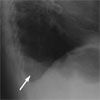

A CT scan confirmed the displacement of the entire stomach into the chest; the lung parenchyma was considerably displaced by the herniation. The shape of the gastric contour is clearly visible on the right side of the chest, and a gastric air-fluid level is present (B, arrow).